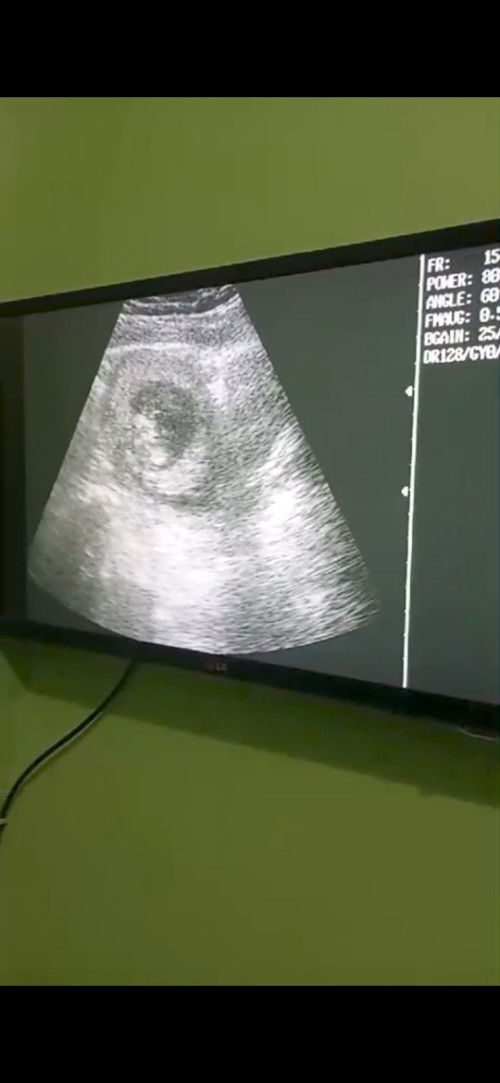

Pendarahan hebat di usia 12weeks,

Pendarahan di usia 12 weeks, udah usg dan kata bidannya disuruh bed rest total. Janin dan detak jantung masih aktif, takut banget karena pernah keguguran. Mungkin karena kecapekan, kemarin naik motor sendiri, emang salah aku sih ini. #sharing #Sharing_dong_Bund biar tidak bosan saat bedrest harus baca apa? Makasih